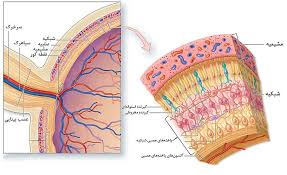

قیمت: 49٬000 تومان - دسته بندی فایل: تحقیقپاورپوینت دستگاه عصبی مرکزی (ppt) 27 اسلاید

فروش ویژه پاورپوینت حرفه ای دستگاه عصبی مرکزی / تعداد اسلاید: 27 اسلاید

قیمت: 59٬000 تومان - دسته بندی فایل: تحقیقپاورپوینت نوروآناتومی و نورو فیزیولوژی (ppt) 49 اسلاید

فروش ویژه پاورپوینت حرفه ای نوروآناتومی و نورو فیزیولوژی / تعداد اسلاید: 49 اسلاید